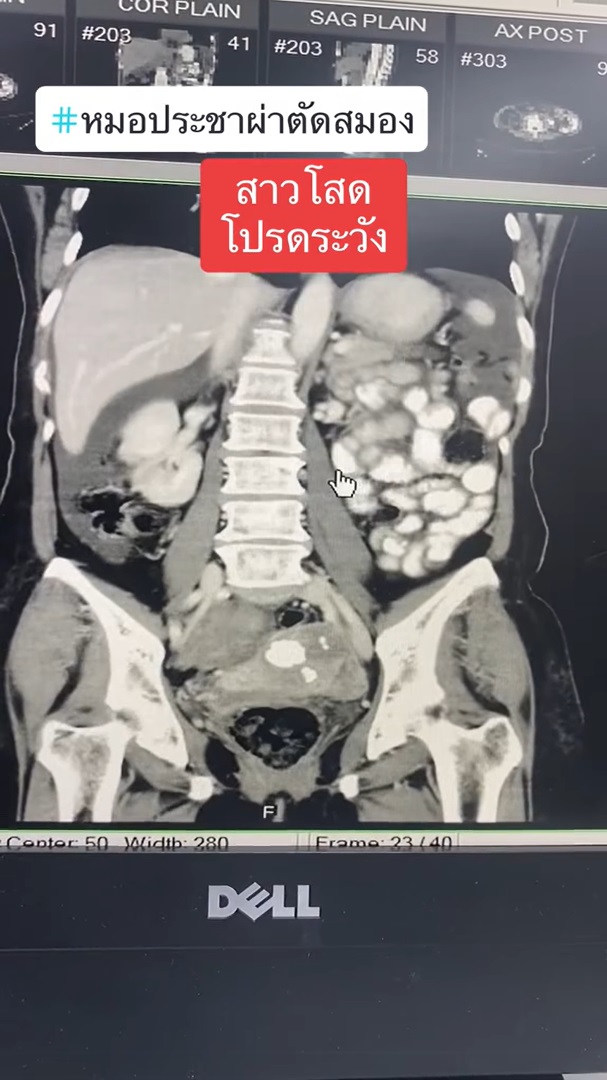

ทำเอาเหล่าสาวโสดถึงกับร้อน ๆ หนาว ๆ หลังจากที่ นายแพทย์ประชา กัญญาประสิทธิ์ หมอผ่าตัดสมอง ออกมาโพสต์เตือนภัยใกล้ตัวที่มีแนวโน้มจะเกิดกับสาวโสดได้ง่ายกว่าคนที่มีลูก โดยได้ยกเคสผ่าตัดเคสหนึ่งมาเป็นกรณีศึกษา ระบุว่า มีผู้ป่วยหญิง อายุ 57 ปี เป็นสาวโสดอยู่คนเดียว มาหาหมอด้วยอาการพูดจาสับสน ซึ่งผลการตรวจเอกซเรย์ พบว่า มีสมองตายหลายจุด ตายทั้งข้างหน้า ข้างหลัง ลามไปจนถึงท้ายทอย ทำให้ตามัว และมีจุดเลือดออกในหย่อมที่สมองตายด้วย และยังตรวจพบอีกหลายอย่าง อาทิ

โดยเคสนี้มาตรวจเนื่องจากญาติร้อนใจ หาสาเหตุไม่ได้ว่าทำไมสมองตายมากขนาดนี้ ก่อนจะเจอแจ็กพอตว่ามีก้อนเลือดเบ้อเริ่มอยู่ในอุ้งเชิงกราน ซึ่งอายุ 57 ปี ไม่ใช่การตั้งครรภ์อย่างแน่นอน พอเอาชิ้นเนื้อไปตรวจพบว่าเป็นมะเร็งรังไข่แล้วทำให้เกิดภาวะลิ่มเลือดไปอุดเส้นเลือดที่อวัยวะต่าง ๆ ของร่างกาย

แคลเซียมก็สูงมาก จากลักษณะของมะเร็ง ไม่ใช่กระจายไปที่สมอง ลิ่มเลือดอุดตันที่ขาสองข้าง ทำให้ขาบวม ทั้งยังเกิดลิ่มเลือดอุดตันในสมองหลายตำแหน่ง คนไข้จึงมาด้วยอาการพูดจาสับสน สุดท้ายกลายเป็นมะเร็งรังไข่ ซึ่งเคสนี้ก็ต้องผ่าตัดและสู้กับมะเร็งรังไข่กันต่อไป